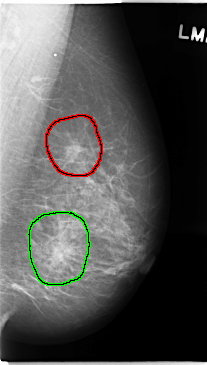

C_0137_1.LEFT_MLO

LEFT_MLO LINES 4736 PIXELS_PER_LINE 2680 BITS_PER_PIXEL 12 RESOLUTION 50 OVERLAY

FILE: C_0137_1.LEFT_MLO.OVERLAY

TOTAL_ABNORMALITIES 2

ABNORMALITY 1

LESION_TYPE MASS SHAPE ARCHITECTURAL_DISTORTION MARGINS SPICULATED

ASSESSMENT 5

SUBTLETY 5

PATHOLOGY MALIGNANT

TOTAL_OUTLINES 1

BOUNDARY

ABNORMALITY 2